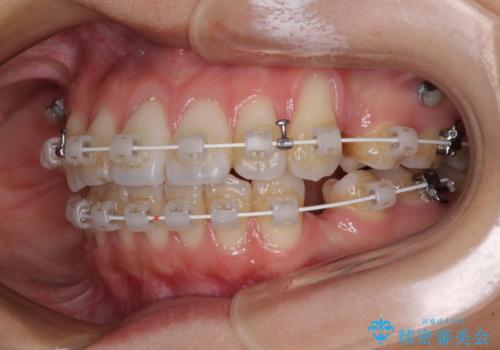

- 審美装置

- 八重歯と口元の突出感を気にして来院された患者様です。

歯列が前方に突出しており、上下の正中がズレていたため、左側は上下第一小臼歯を、右側は上下第二小臼歯を抜去し、ワイヤー装置による矯正治療を行うこととしました。

当初はインビザラインによる矯正治療をご希望でしたが、正中を合わせたいことや、口元の突出感を改善したいことから、ワイヤー矯正を強く推奨しました。

治療期間は2年に満たず、スッキリとした口元に仕上がりました。